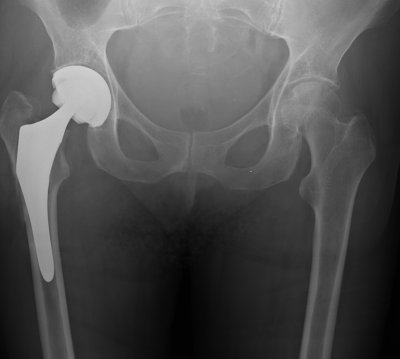

Слева на изображении Вы видите корректно установленный эндопротез правого тазобедренного сустава. Это наиболее частый способ замены ТБС, он самый долговечный и прочный.